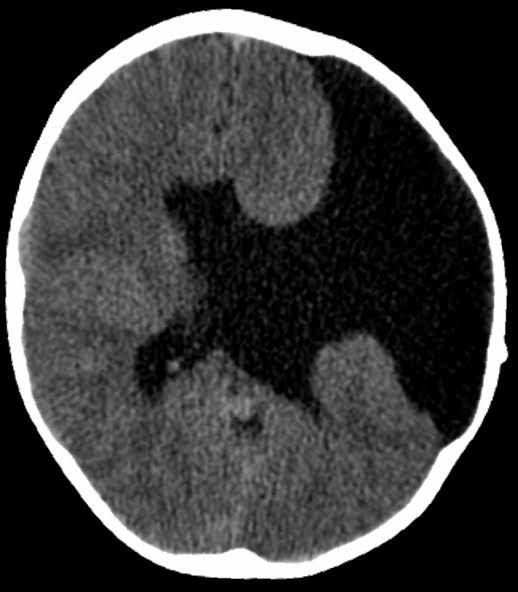

Schizencephaly is a rare congenital (present from birth) brain malformation in which abnormal slits or clefts form in the cerebral hemispheres of the brain. The signs and symptoms of this condition may include developmental delay, seizures, and problems with brain-spinal cord communication.